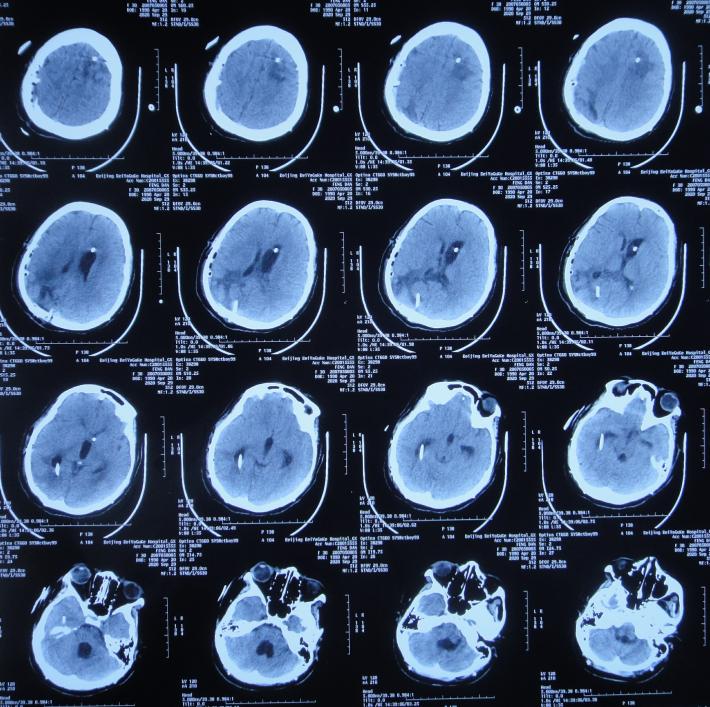

开颅术后15天即2020年4月17日(腰大池引流术后7天),查头颅CT示仍脑膨出( 图-4 ),因腰大池引流管堵塞,给予拔除并第2次重新置换腰大池。

图-4: 2020年4月17日头颅CT